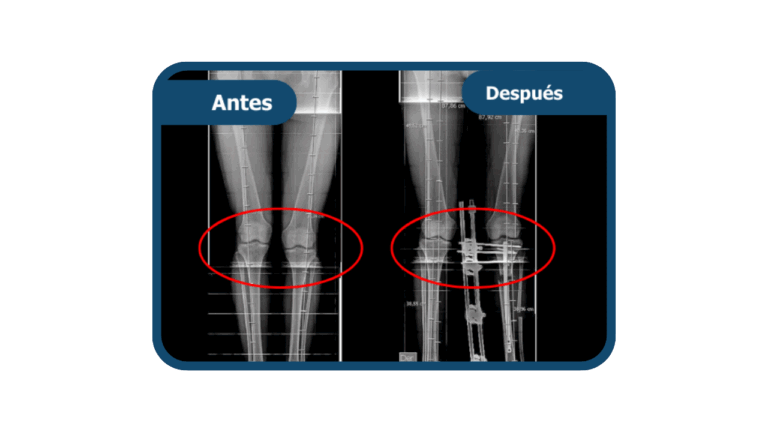

Genu valgo

Es una deformidad en la que las rodillas se desvían hacia adentro, generando una separación entre los tobillos y alterando la alineación de las piernas. Puede causar dolor, inestabilidad y desgaste articular. En Clínica Arthrosalud puede ser tratada por nuestros traumatólogos especialistas.

El tratamiento depende de la revisión profesional y el grado de la deformidad. En casos leves, se maneja con control médico y terapia física. En casos moderados o severos, se corrige mediante una osteotomía, cirugía que permite realinear el hueso y restaurar la correcta alineación de la pierna.